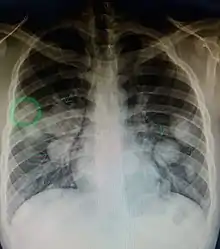

Pulmonary metastases shown on Chest X-Ray

The cells in a metastatic tumor resemble those in the primary tumor. Once the cancerous tissue is examined under a microscope to determine the cell type, a doctor can usually tell whether that type of cell is normally found in the part of the body from which the tissue sample was taken.

For instance, breast cancer cells look the same whether they are found in the breast or have spread to another part of the body. So, if a tissue sample taken from a tumor in the lung contains cells that look like breast cells, the doctor determines that the lung tumor is a secondary tumor. Still, the determination of the primary tumor can often be very difficult, and the pathologist may have to use several adjuvant techniques, such as immunohistochemistry, FISH (fluorescent in situ hybridization), and others. Despite the use of techniques, in some cases the primary tumor remains unidentified.